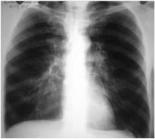

Рентгенологическое исследование легких и сердца. Характерными при-

знаками эмфиземы легких являются низкое расположение купола диафрагмы и ее уплощение, заметно сниженная экскурсия диафрагмы; повышенная воздушность легочных полей; увеличение ретростернального пространства (признак Соколова); обеднение легочных полей сосудистыми тенями (сосудистый рисунок приобретает нитеобразный характер и значительно ослабевает к периферии). Сердечная тень сужена, вытянута («капельное сердце»).